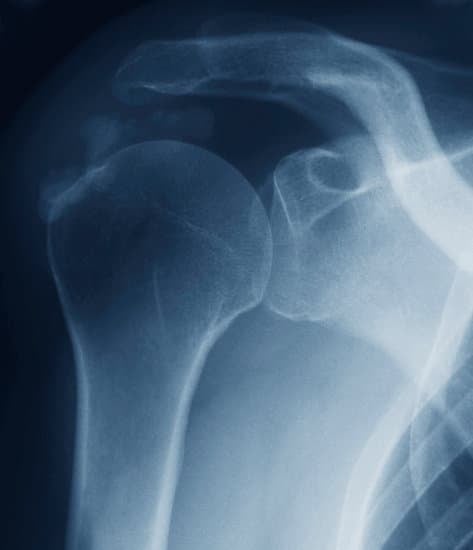

회전근개 손상: 이해, 예방 및 치료

회전근개는 어깨를 구성하는 네 개의 근육과 그 힘줄로 이루어진 집합체로, 팔의 움직임을 돕고 어깨 관절의 안정성을 유지하는 데 중요한 역할을 합니다.

이 근육들은 팔을 들어 올리거나 회전하는 동작을 가능하게 합니다.